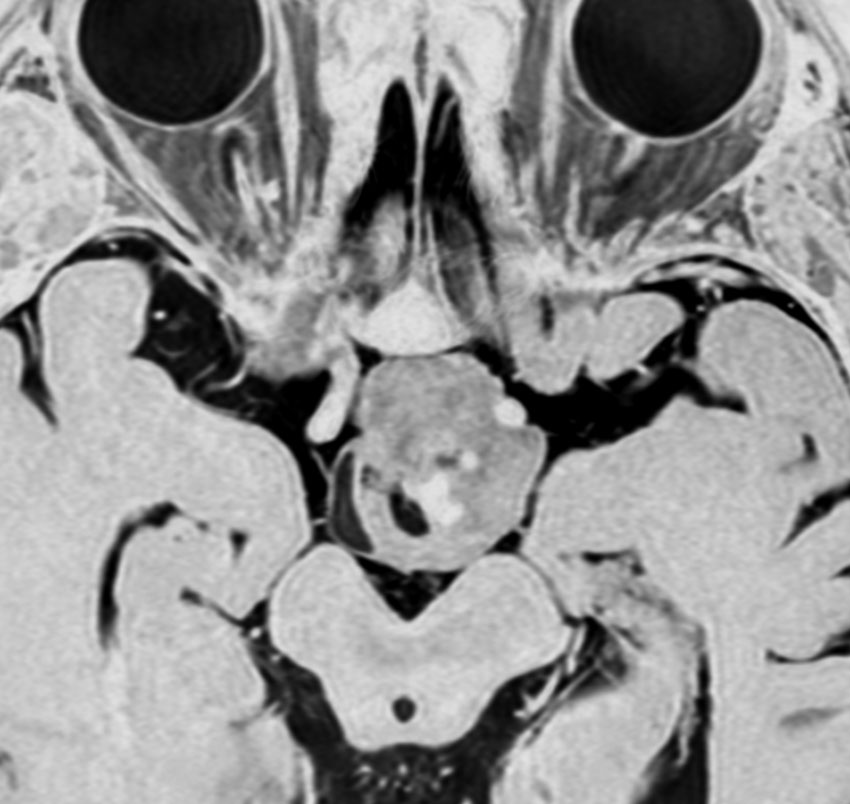

全く何もしなくても良い成人の毛様細胞性星細胞腫

20代女性に偶然発見された視床下部(第3脳室)腫瘍です,T1低信号,T2で高信号,右側のガドリニウム造影では全く増強されません。毛様細胞性星細胞腫と診断できます。眼科での視野検査で視野欠損はありませんでした。生検術もなにもせず経過をみました。

左が初診時,右が5年後のMRI画像です。腫瘍の大きさは全く同じです。このような腫瘍はしばしば経験します。慌てて生検術や開頭手術など計画しないで,画像診断をしっかりすることが大切です。